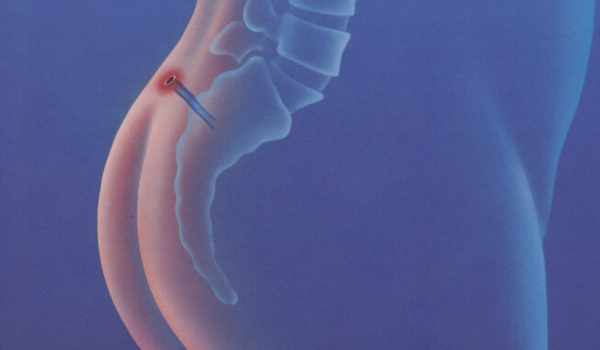

Quistes intergluteos que aparecen posterior a una infección.

Resultados de un estudio de cohorte multicéntrico sobre el cierre asistido por láser sinusal (SiLaC®) para enfermedad pilonidal, evaluando seguridad, eficacia y satisfacción del paciente.